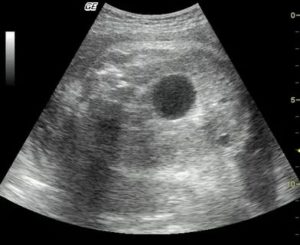

Из очаговых изменений чаще всего в почках выявляют кисты. Они выглядят как анэхогенные (полностью черные) структуры округлой формы с ровными отчетливыми контурами, дающие за собой усиление ультразвукового сигнала.

Может быть видно только одну кисту, но чаще их бывает несколько в одной или обеих почках. Как правило, никакой опасности простые кисты не представляют и встречаются у многих людей после 40 лет.

- Кистозные образования. Имеют вид анэхогенных (чёрных полностью) образований или пятен. Контуры у таких кист ровные, а форма округлая. При кистах сигнал ультразвука усиливается.

Совсем черный оттенок имеют:

- Киста;